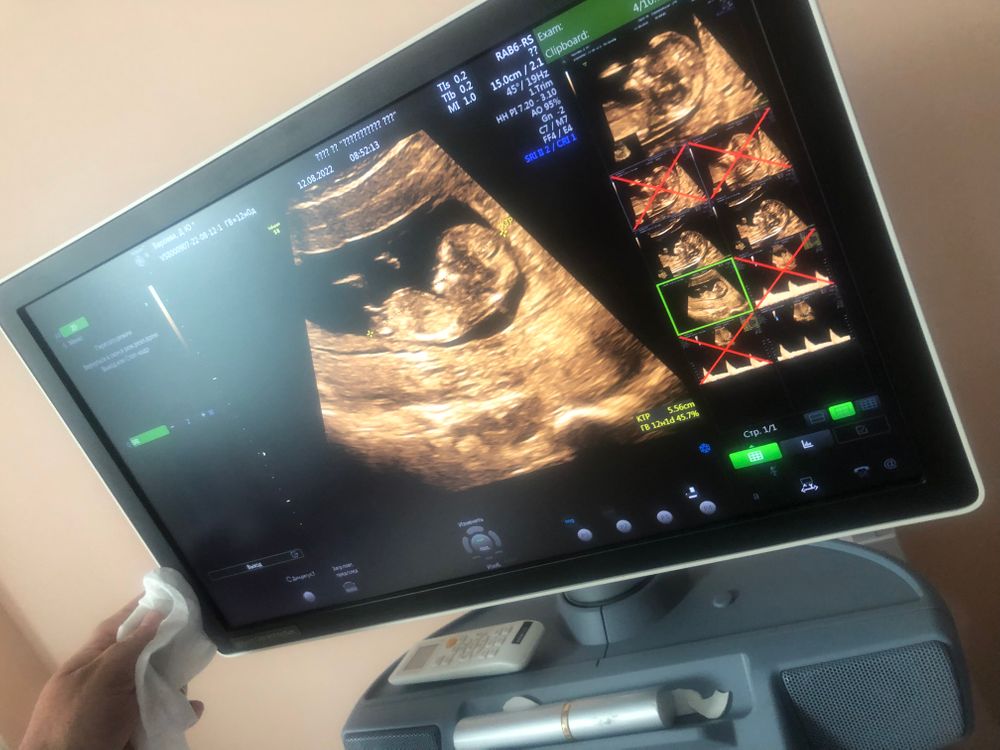

Угадываю пол в 13 недель)

Изображение Вот у моей девочки, если это бугорок, конечно 🤷🏻‍♀️🤣 тоже в 12 недель вся изгадалась🤦🏻‍♀️

Судя по углу наклона полового бугорка - мальчик) у девочек он более горизонтально расположен

Точно мальчишка) у моего такой же бугорок был в 12,4, слегка вверх Изображение